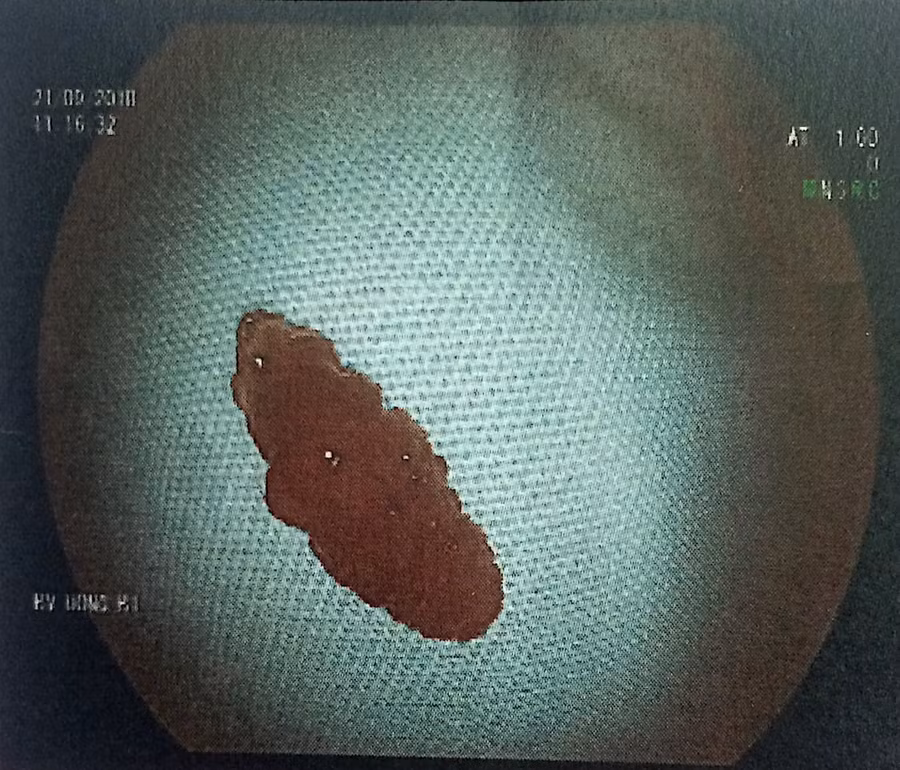

| Con sán trong dạ dày người bệnh |

Tuy nhiên, theo ThS. Bác sĩ Đỗ Quang Út - Phó Trưởng khoa Nội tiêu hóa Bệnh viện Việt Nam-Thụy Điển Uông Bí (Quảng Ninh), sán lá gan vào cơ thể người qua thực phẩm bị nhiễm mầm bệnh. Chúng ký sinh chủ yếu ở gan và đường mật, một số ít trường hợp sán di chuyển xuống ruột có thể quan sát thấy khi nội soi đường tiêu hóa.